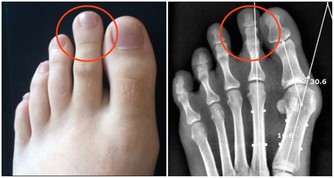

3. 鞏膜發黃:肝炎

鞏膜發黃是臨床上診斷肝病的重要依據,甲肝、急性乙肝患者大多都有不同程度的鞏膜發黃症狀。

如果出現角膜色素環,這是肝豆狀核變性患者的主要特徵。

據統計,此病的遺傳性發生率可佔此病患者的90%。

用肉眼可見環繞角膜、邊緣寬約2-3mm的黃綠色、藍綠色或棕黃色環狀帶。